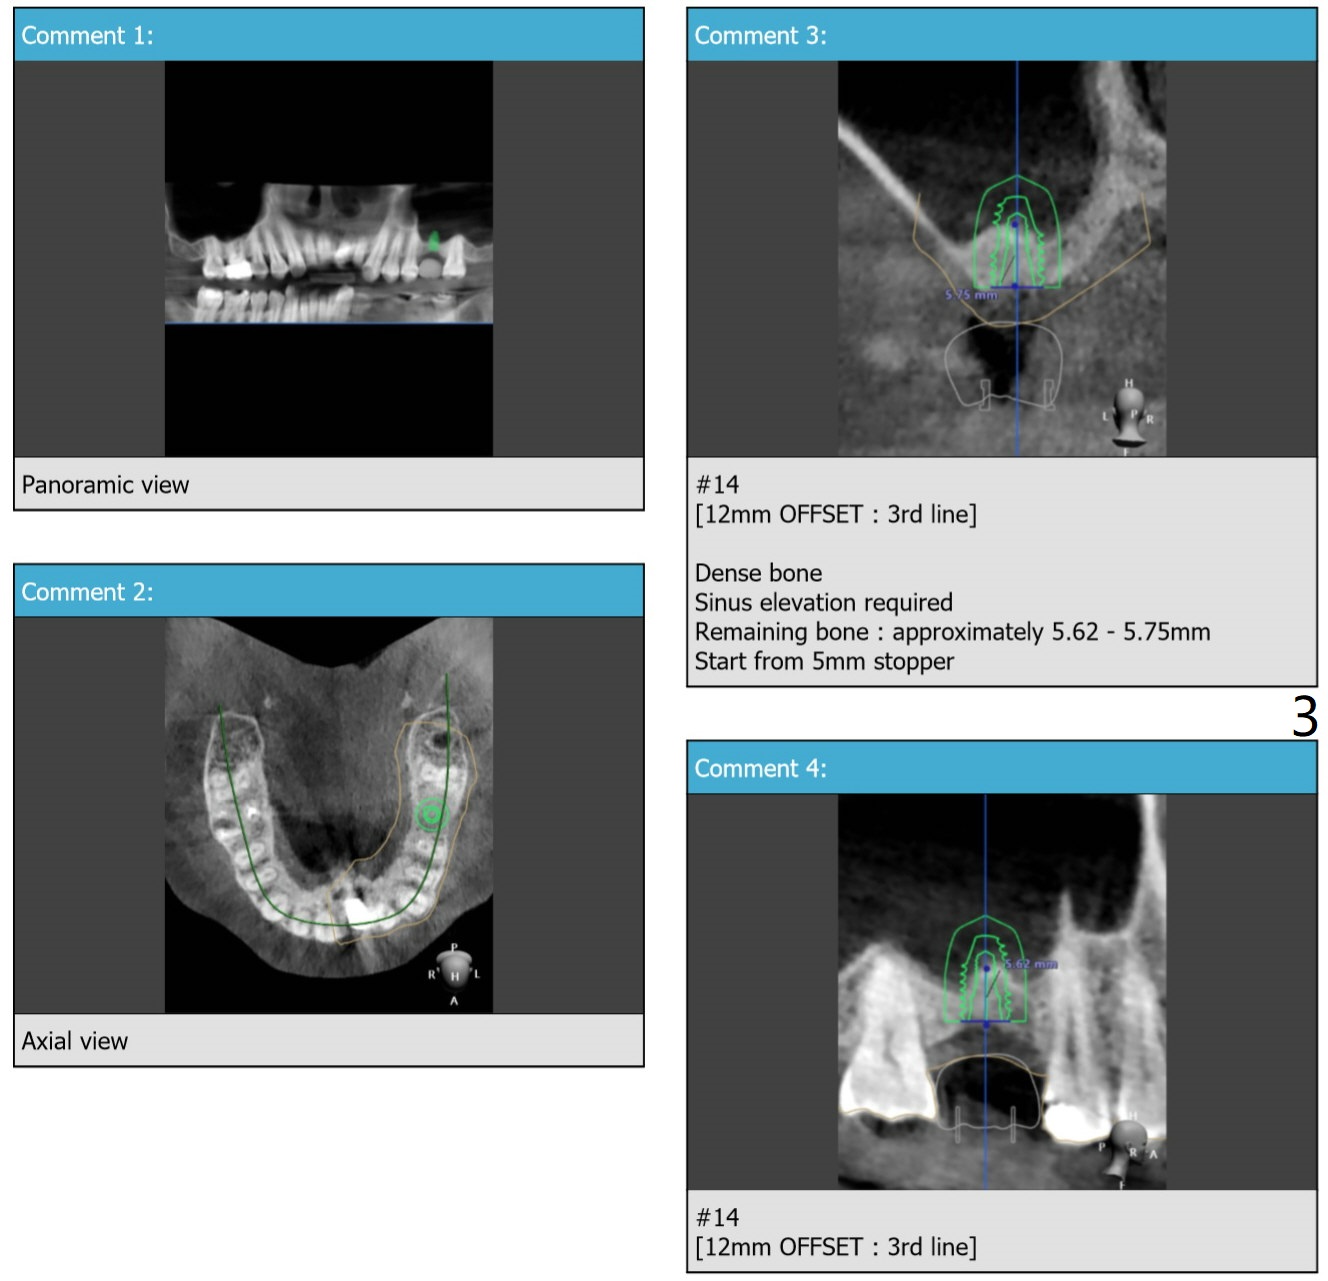

Implant Redo with Sinus Lift I

Return to No Deviation

Xin Wei, DDS, PhD, MS 1st edition 02/21/2020, last revision 06/05/2020